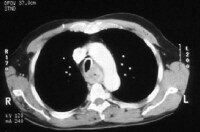

Workup of common cancers medclerk med.Unc.Edu. Nov 10, 2015 gastric cancer is the third most common cause of cancerrelated death in gastric cancer workup. Author elwyn c cabebe, md; chief editor n joseph. Acr appropriateness criteria® stage i breast cancer. Acr appropriateness criteria® stage i breast cancer initial workup and surveillance for local recurrence and distant metastases in asymptomatic women. Stomach cancer warning. Search for metastatic cancer. Find expert advice on about. Biliary sludge symptoms? Gastroenterology medhelp. Hello. I've been having digestive symptoms of increasing severity for about two years, now. At first, i thought it was due to my chronic sinusitis. Basically, i have. Bladder cancer workup medscape reference. · bladder cancer is a common urologic cancer. Almost all bladder cancers originate in the urothelium, which is a 3 to 7cell mucosal layer within the. Cancer blood tests lab tests used in cancer. May 02, 2016 renal cell carcinoma (kidney cancer) testicular cancer; the abdominal ct scan may show problems with the gallbladder, liver, or pancreas, including.